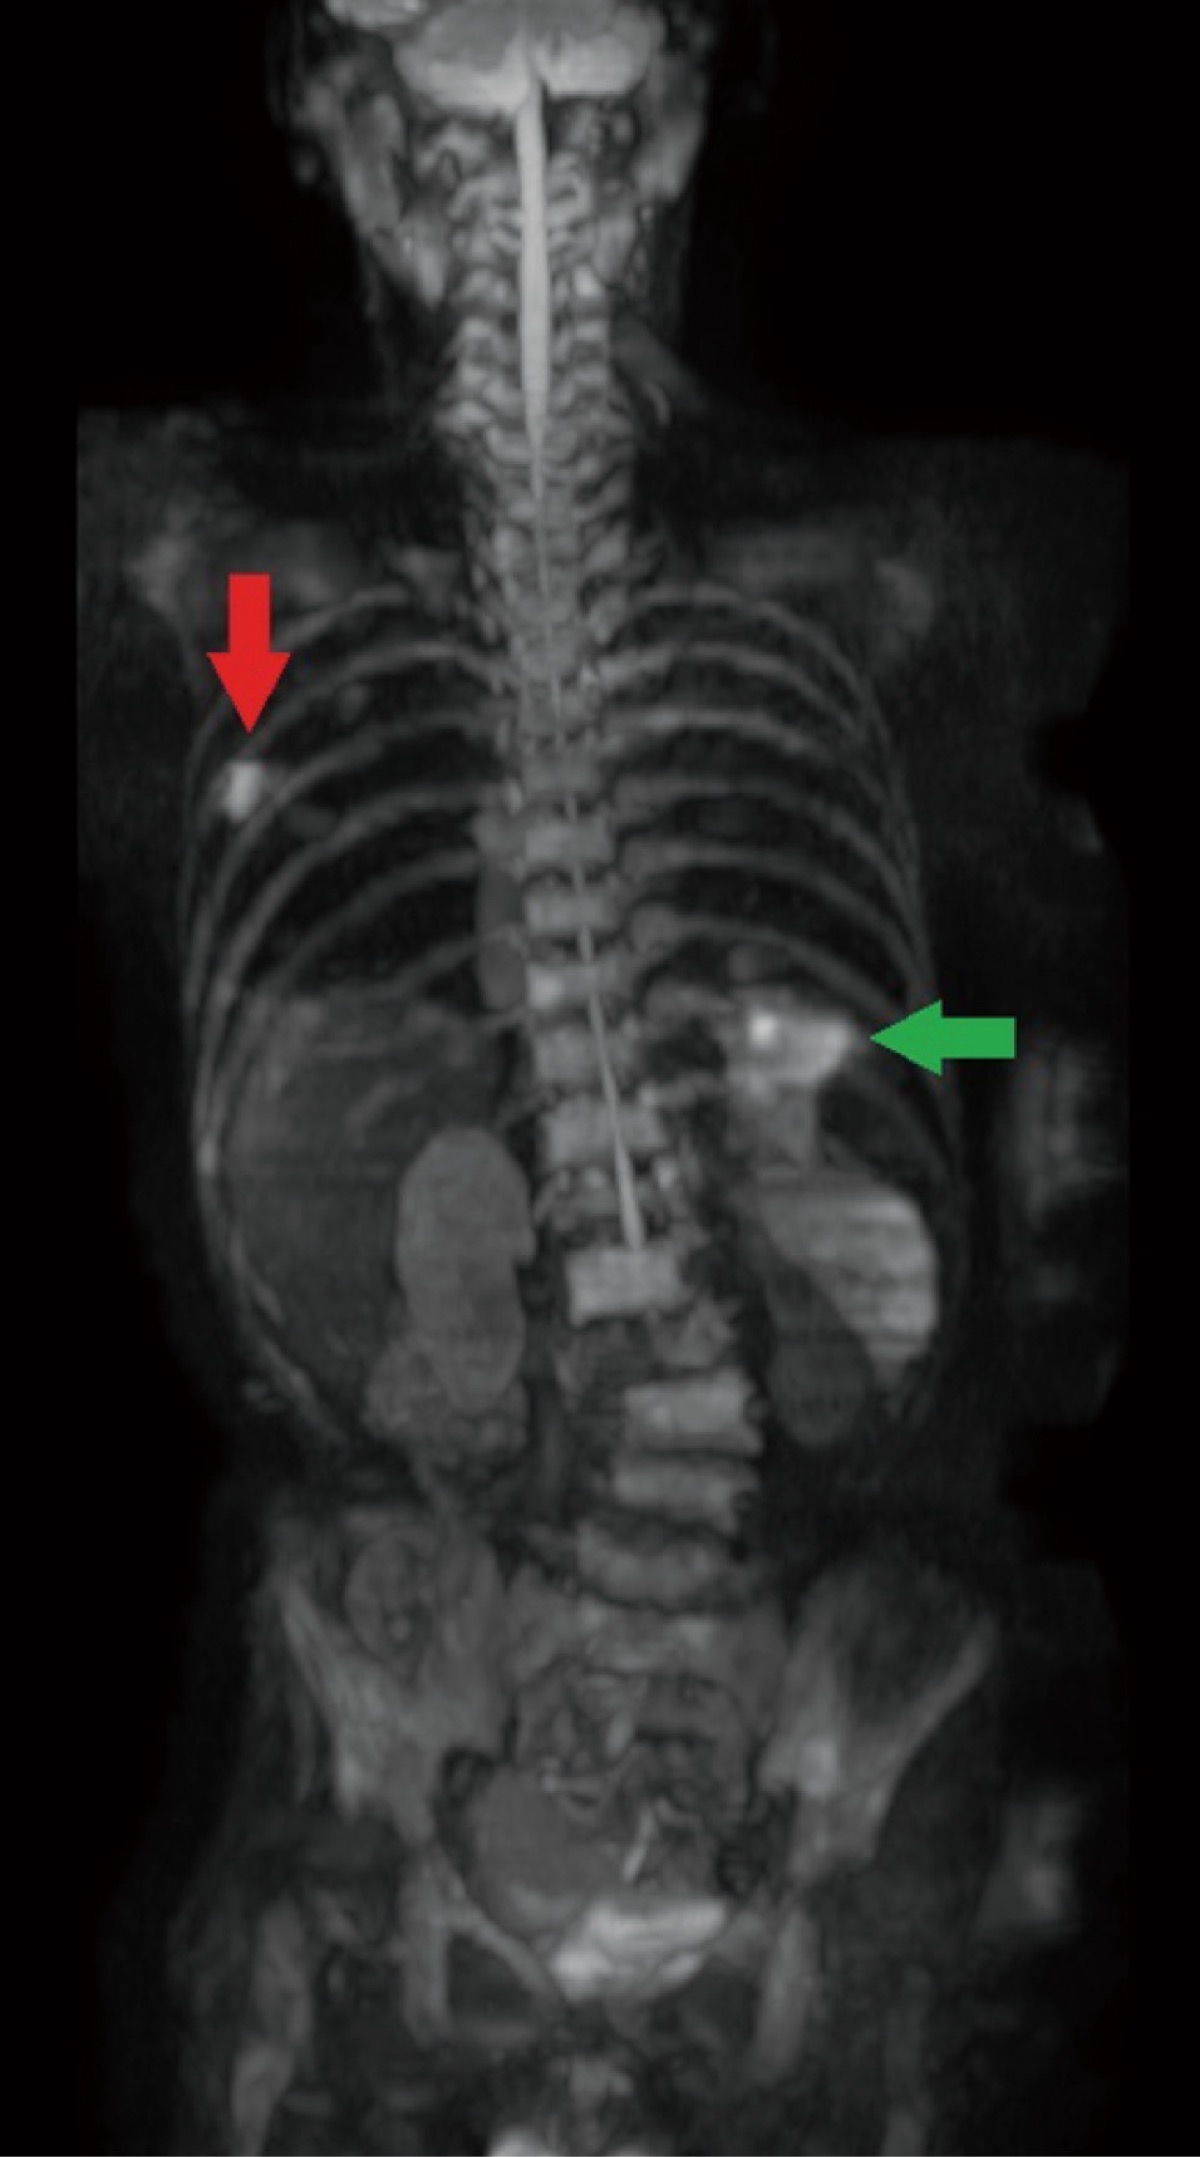

全身のがんの画像検査というとPET検査が有名だが、どのような違いがあるのか。曾根氏は「全身MRI検査は放射線被曝が無く繰り返し行えること、短時間、PET検査に比べ安価であることが特徴です。但しPET検査同様にMRI検査で異常が見つかっても全てが悪性腫瘍ではない所が注意点。左の写真でも左右に集積がありましたが、内視鏡などの追加検査で、赤矢印は肺癌であることがわかり手術、緑矢印は炎症による変化であることがわかりました。この様に見つけるだけの画像検査ではなく精密検査や治療につなげる体制があることが当院の特徴。全身MRI検査を通して質の高い地域医療を目指したい」と話す。